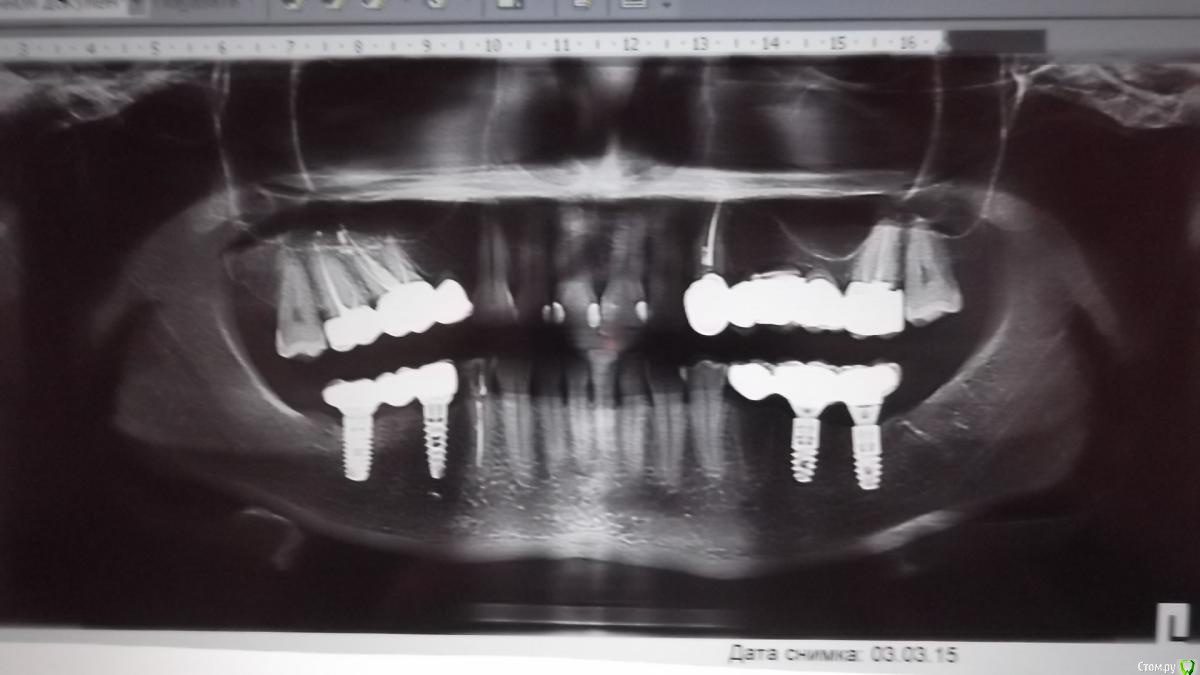

o_lena Опубликовано 24 августа, 2018 Автор Поделиться Опубликовано 24 августа, 2018 Здравствуйте, уважаемые специалисты!Шесть лет уже хожу с имплантами, способ фиксации коронок: цементируются.Цемент держится два года или чуть больше, т.е. за этот срок уже трижды переклеивала, хожу в одну и ту же клинику.Прошу вашего совета: два года условно-постоянного цемента это стандартно или существуют другие, более долговечные цементы?Снимок размещен выше. Ссылка на комментарий

o_lena Опубликовано 28 августа, 2018 Автор Поделиться Опубликовано 28 августа, 2018 Ссылка на комментарий

red_butler Опубликовано 29 августа, 2018 Поделиться Опубликовано 29 августа, 2018 по снимкам все не плохо, если расцементировки будут повторятся, стоит задуматься о замене конструкции Ссылка на комментарий